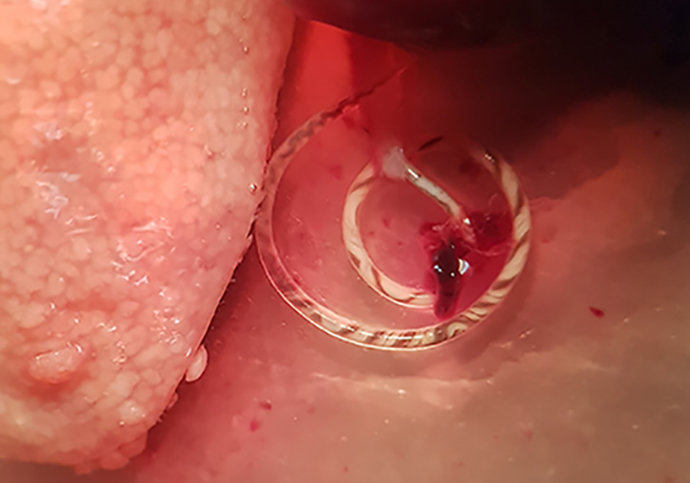

Angiostrongylus cantonensis emergiendo de la arteria pulmonar de una rata capturada en zona de huerta de Valencia

Angiostrongylus cantonensis emergiendo de la arteria pulmonar de una rata capturada en zona de huerta de Valencia - UGR

Una investigación en la que participan científicos de la Universidad de Granada (UGR) ha hallado por primera vez en Europa continental el gusano Angiostrongylus cantonensis, un parásito capaz de ser transmitido al ser humano presente en las arterias pulmonares de las ratas y que es el agente causal más común en el ser humano de la meningitis eosinofílica (ME).

El grupo de investigación Parásitos y Salud, del Departamento de Farmacia y Tecnología Farmacéutica, y Parasitología de la Facultad de Farmacia de la Universidad de Valencia está trabajando en colaboración con el Servicio de Sanidad del Ayuntamiento de esta ciudad y la empresa Laboratorios Lokímica, responsable del control de plagas, en un estudio parasitológico de los roedores en la capital valenciana. El descubrimiento, de importante repercusión en Salud Pública, del nematodo se ha dado tanto en rata de alcantarilla (Rattus norvegicus) como en la negra (Rattus rattus).